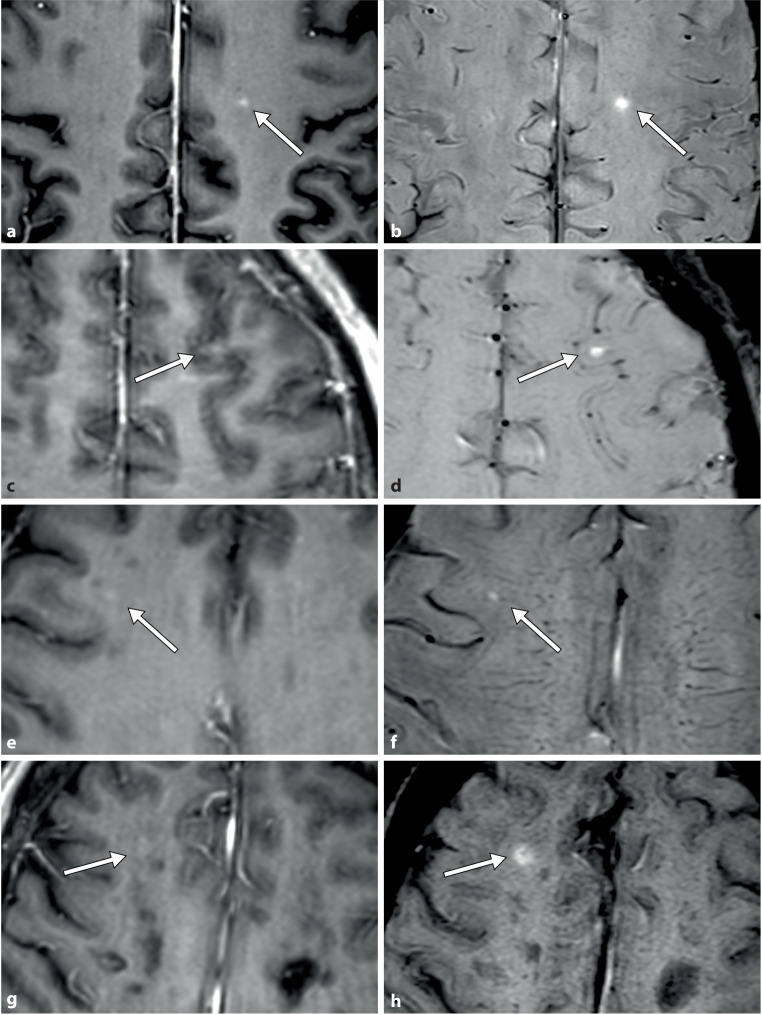

Objectives: MRI is essential for monitoring multiple sclerosis (MS). Contrast-enhanced T1-weighted imaging (T1WI+C) detects active inflammatory lesions indicating blood-brain barrier breakdown and is relevant for disease monitoring and treatment optimization. Susceptibility-weighted imaging (SWI) may be included in the imaging protocol for detecting MS-specific features, such as the presence of central veins or paramagnetic rim lesions. However, post-contrast SWI (SWI+C) has an inherent "T1 shine-through effect" that enables the visualization of contrast-enhancing lesions. This study evaluates whether SWI+C in addition to standard T1WI+C improves the detection of enhancing lesions in patients with MS.

Materials and methods: The images of 310 patients with MS who underwent a standardized MRI protocol including T1WI+C and SWI+C using a 3T scanner were retrospectively reviewed. A neuroradiologist and radiology resident independently evaluated the images obtained on T1WI+C alone and T1WI+C plus SWI+C. The efficacy of T1WI+C alone was compared with that of T1WI+C plus SWI+C for detecting active enhancing MS lesions.

Results: The neuroradiologist detected 117 lesions on T1WI+C and 123 lesions on T1WI+C plus SWI+C. The resident detected 108 lesions on T1WI+C and 121 lesions on T1WI+C plus SWI+C. The interobserver agreement improved from 0.981 to 1.00 with the addition of SWI+C.

Conclusion: Adding SWI+C to standard T1WI+C consistently enhances the detection of active enhancing inflammatory MS lesions and the interobserver agreement. If standardized, this combined approach may allow for earlier detection of disease activity and improve monitoring of MS progression, potentially leading to optimized treatment decisions and improved patient outcomes.